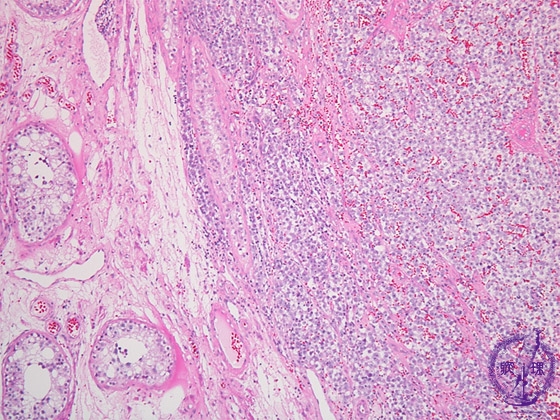

- ★(4)Seminoma (Germ cell tumor)

Histology (HE stain, low power): Large tumor cells proliferated in a solid pattern. On the left side of yellow dotted line, testicular tissues including seminiferous tubules (red dotted line) are compressed by tumor growth.